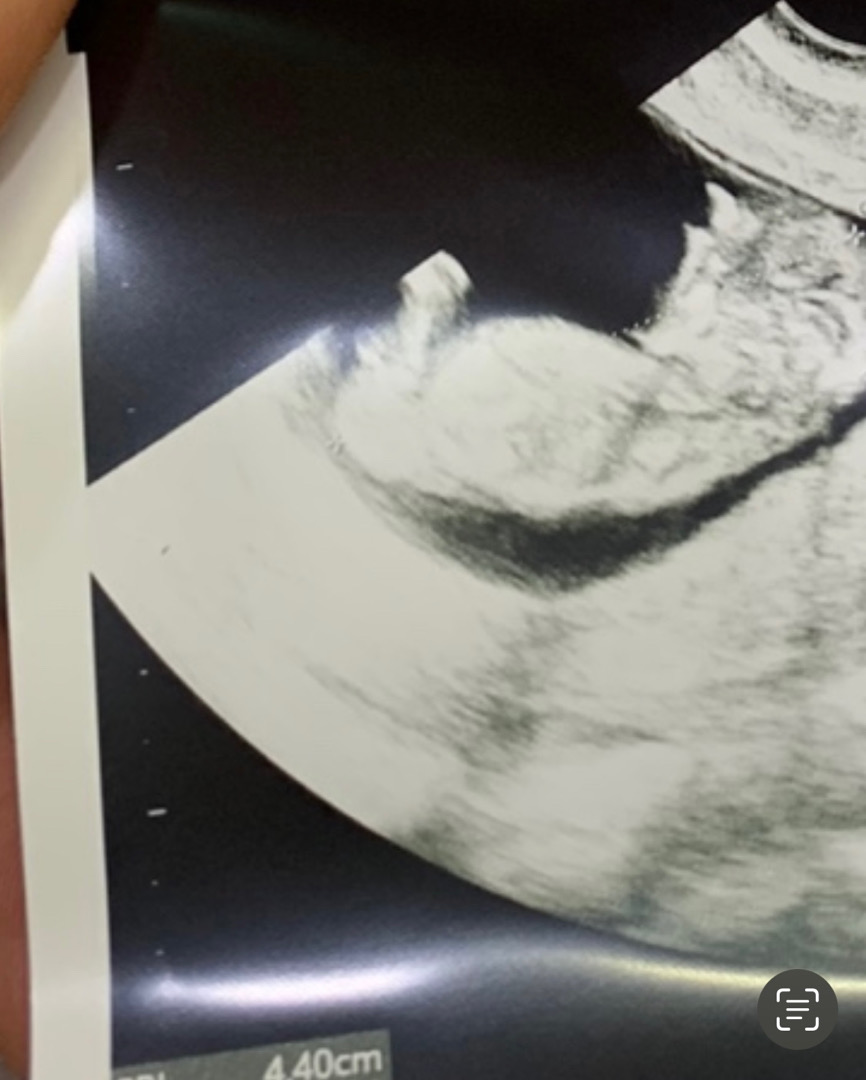

이 사진으로 각도법,, 성별 봐주실 분 있을까요 ? 11주차 초음파 사진이예용 갑자기 궁금해서 게시물 올려봅니당 🤣